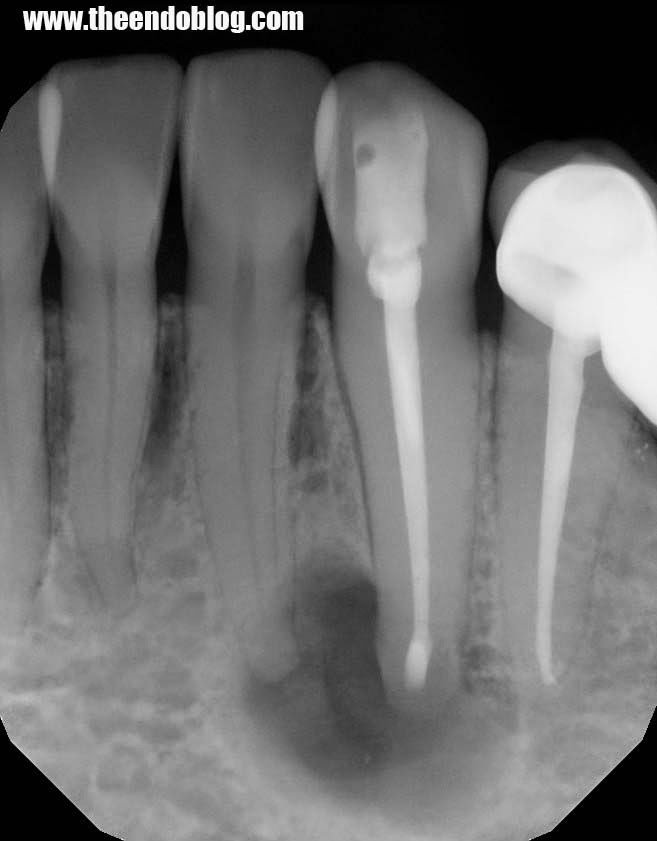

A 42 yr old, white, female presented for evaluation of #22. She was asymptomatic, with a prior RCT on #22. A large nodular, irregular, radiopacity found within a large radiolucent area on the periapical radiograph. Tooth is normal to palpation, percussion and probings.

DX: Prior RCT with possible periapical cemental dysplasia. Apical surgery recommended with biopsy.

Biopsy report indicated Periapical Cemental Dysplasia (anterior focal osseous dysplasia) Recurrence would be unusual, but other areas of dysplasia can arise as well as truamatic bone cysts are also common.